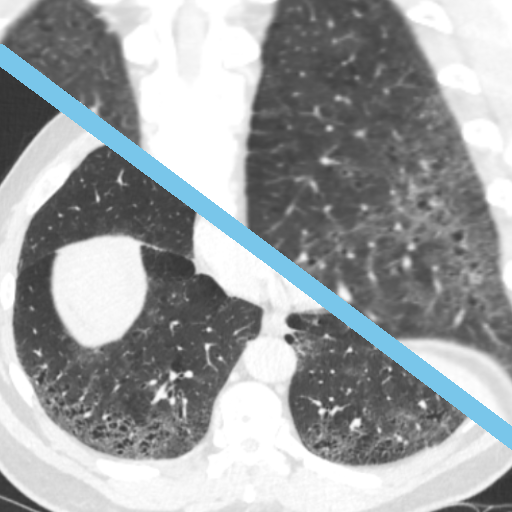

Learn moreInterstitial Lung Disease on HRCT

High-resolution CT (HCRT) is a key diagnostic tool for assessing the extent of Interstitial Lung Disease and exploring possible aetiologies. This package will teach you the manifestations of ILD on HRCT and train you in the fundamentals of interpretation.